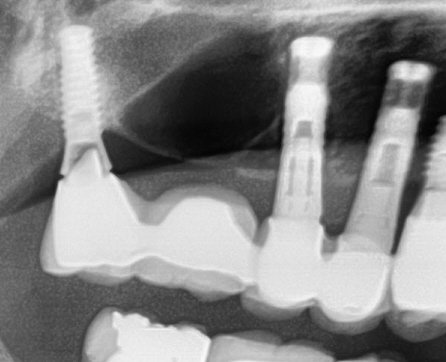

Identificación Implante 47 y tornillo fracturado.

Paciente que acude con corona sobre implante 47 floja. Al destapar para ver si se puede apretar ya extraemos la cabeza del tornillo fracturado y posteriormente conseguimos retirar el fragmento [...]